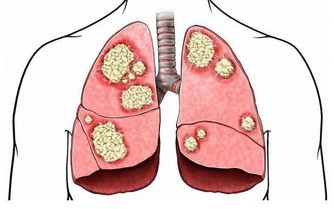

***1、鹹魚:***

這類魚是經過加工處理的,含有很高的鹽分,偶爾吃一下還是可以的,但不能經常吃。國際癌症研究機構已把中國式鹹魚列為第一類致癌物,經常食用會增加鼻咽癌的風險。